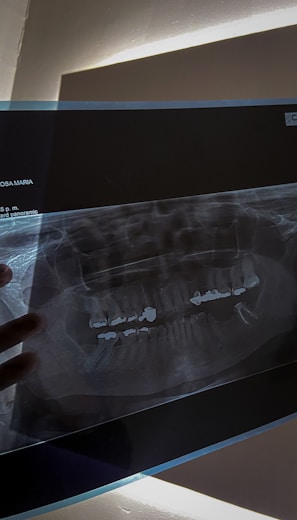

Panoramic Imaging

Comprehensive panoramic imaging solutions for thorough dental and maxillofacial evaluations.

Imaging Gallery

Explore our advanced CT and panoramic imaging services through visuals.